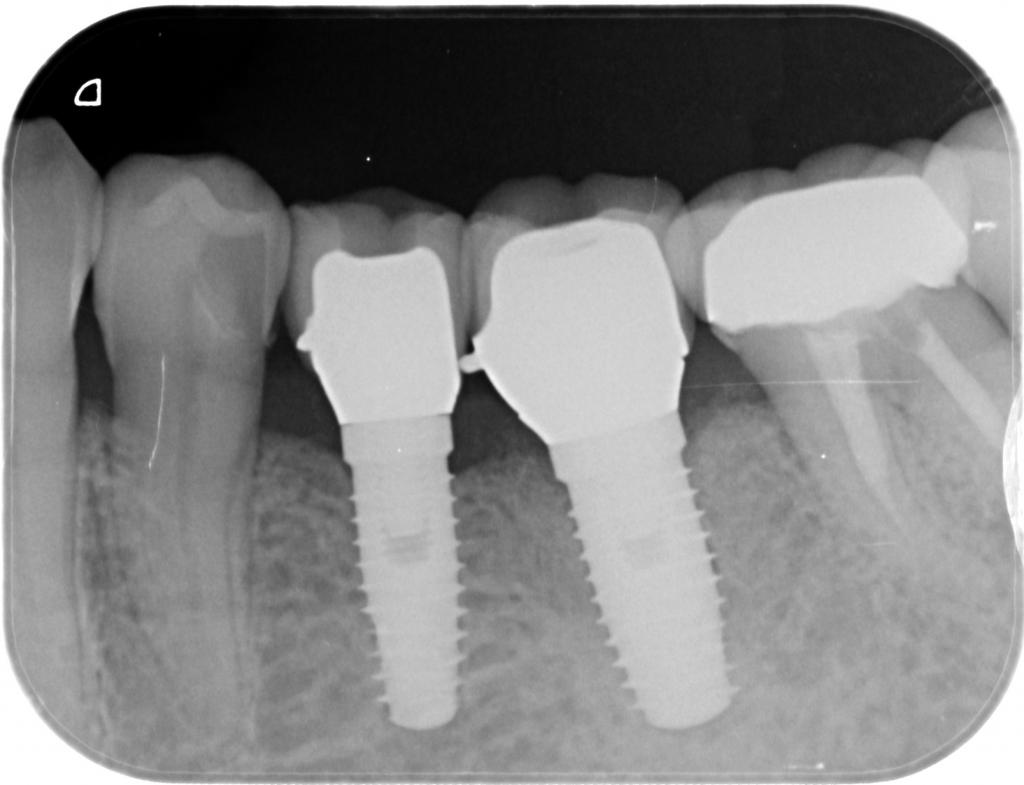

- 埋入直後のレントゲン写真です。

適切な位置に2本、埋入されています。

- 術後のレントゲン写真です。

長さ、方向、共に問題なく植立されています。